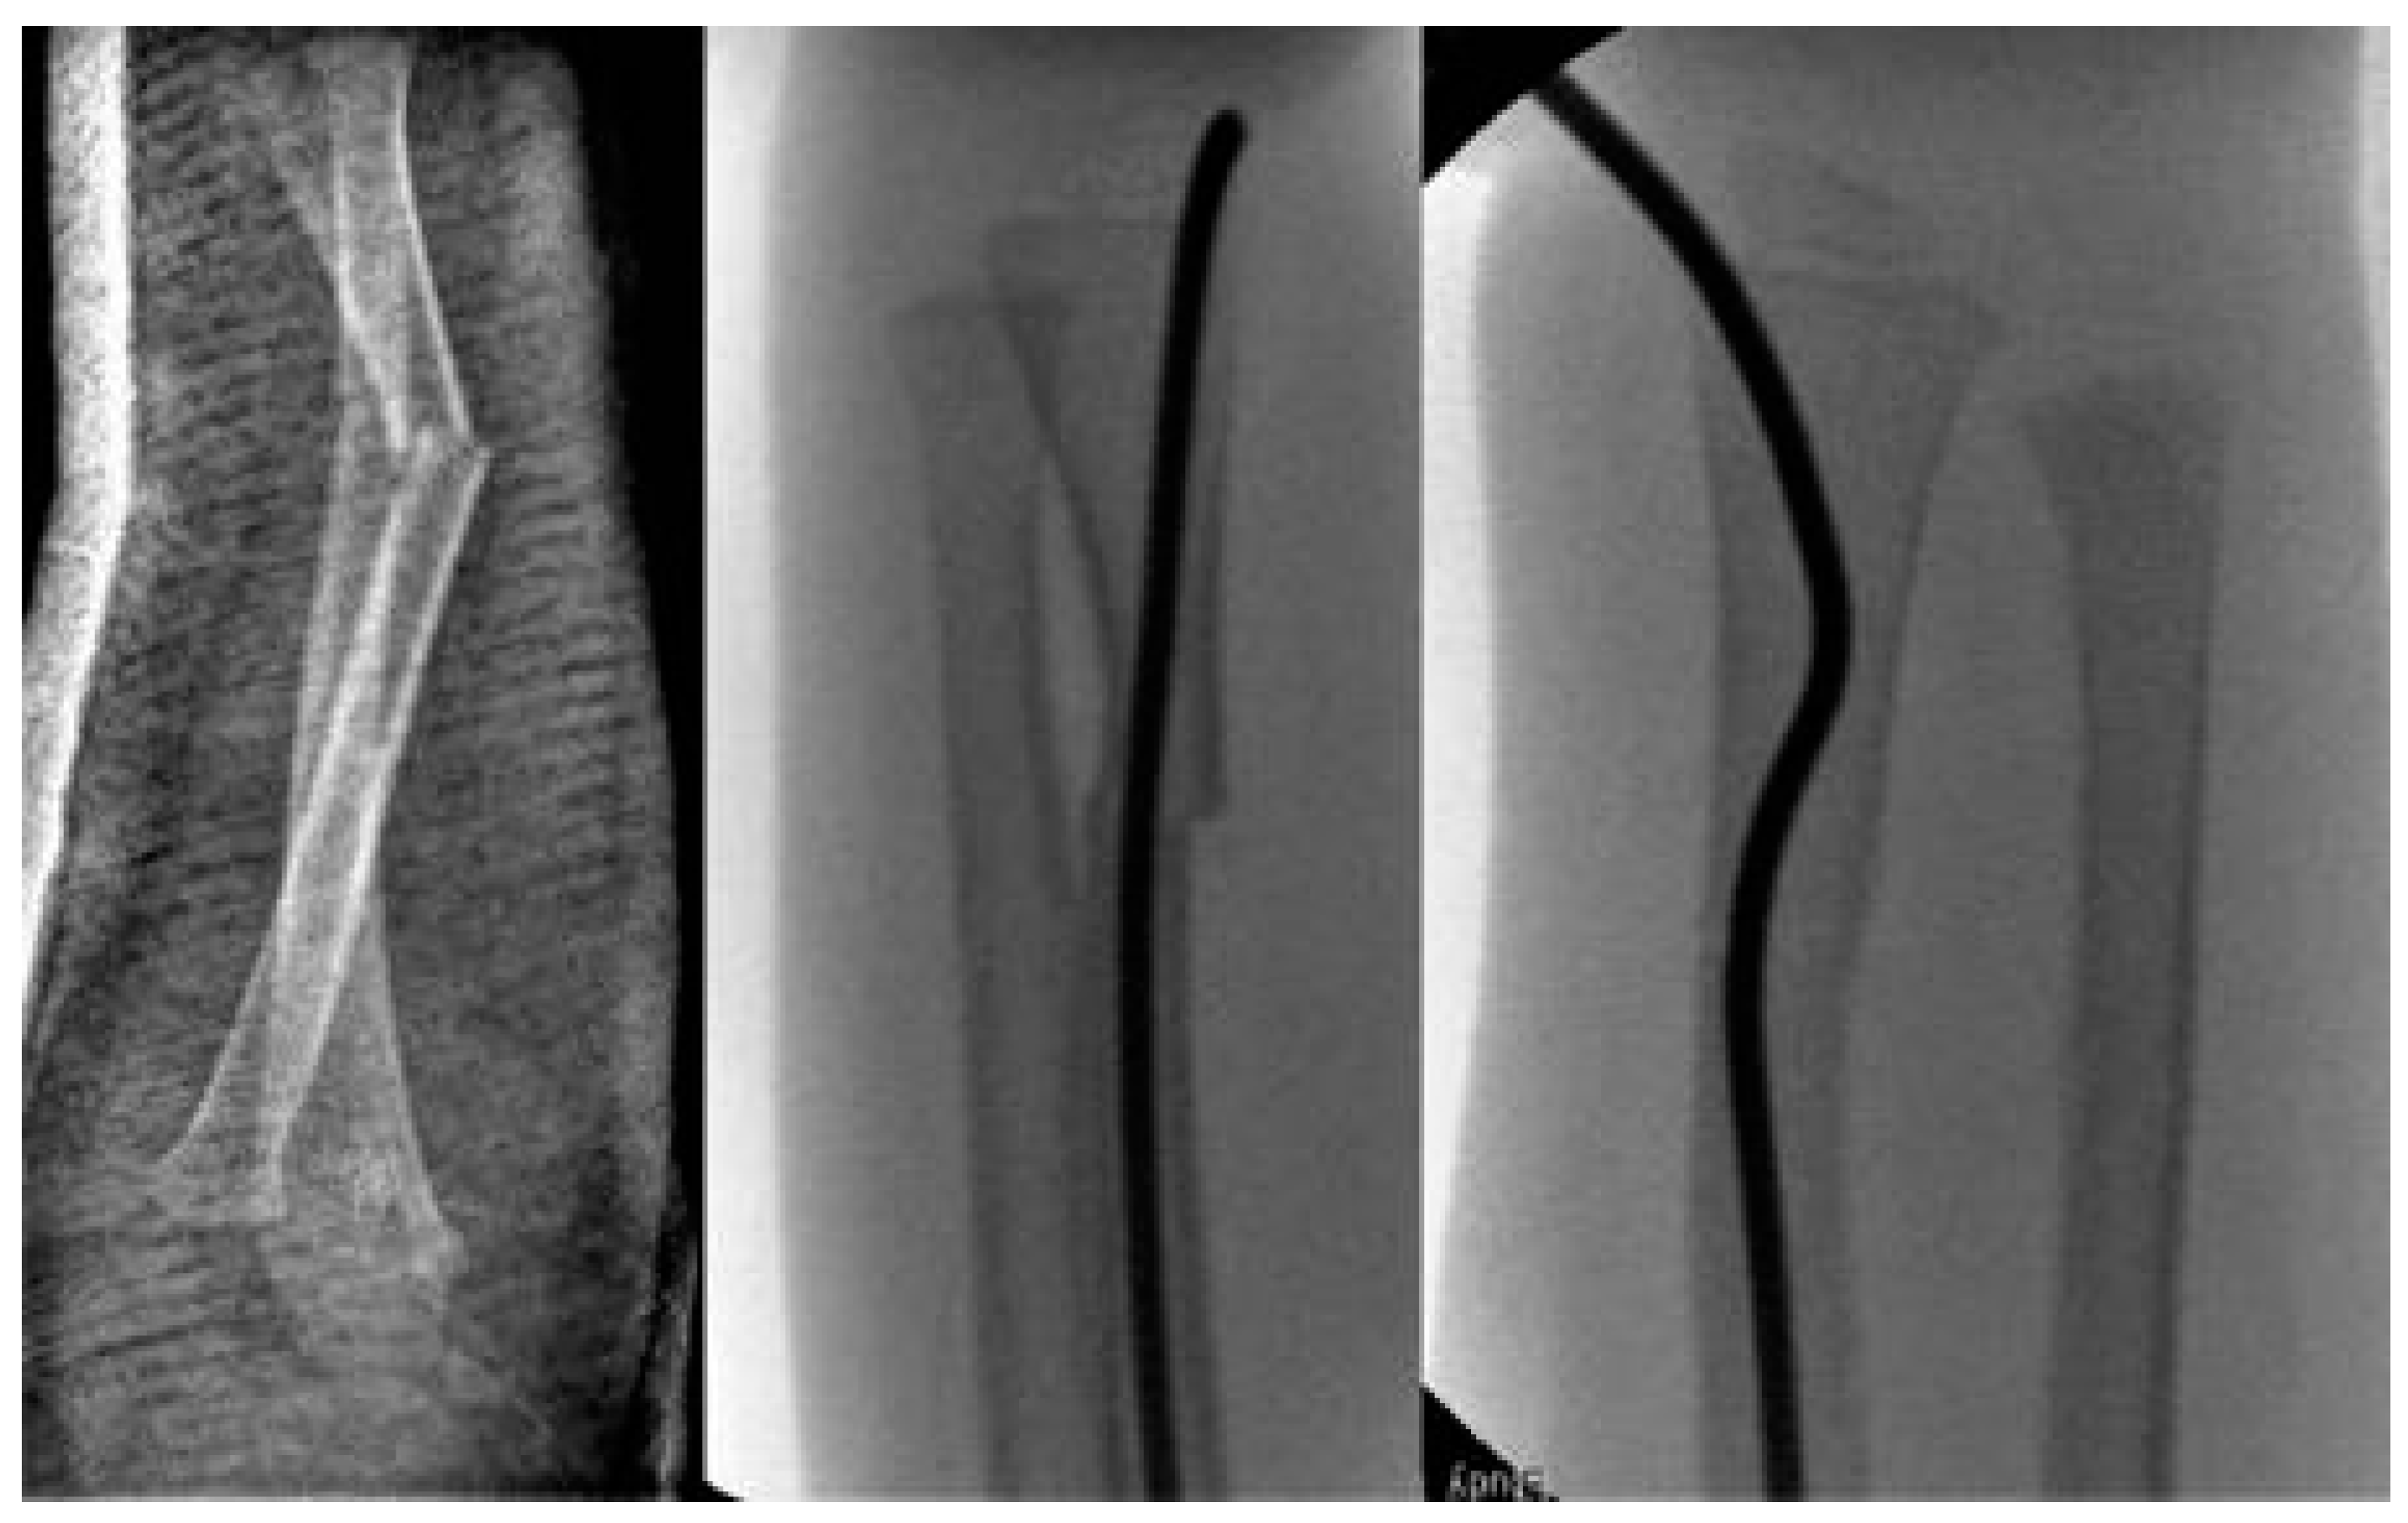

Scheme 2. 2-year-old boy with secondary displacement.